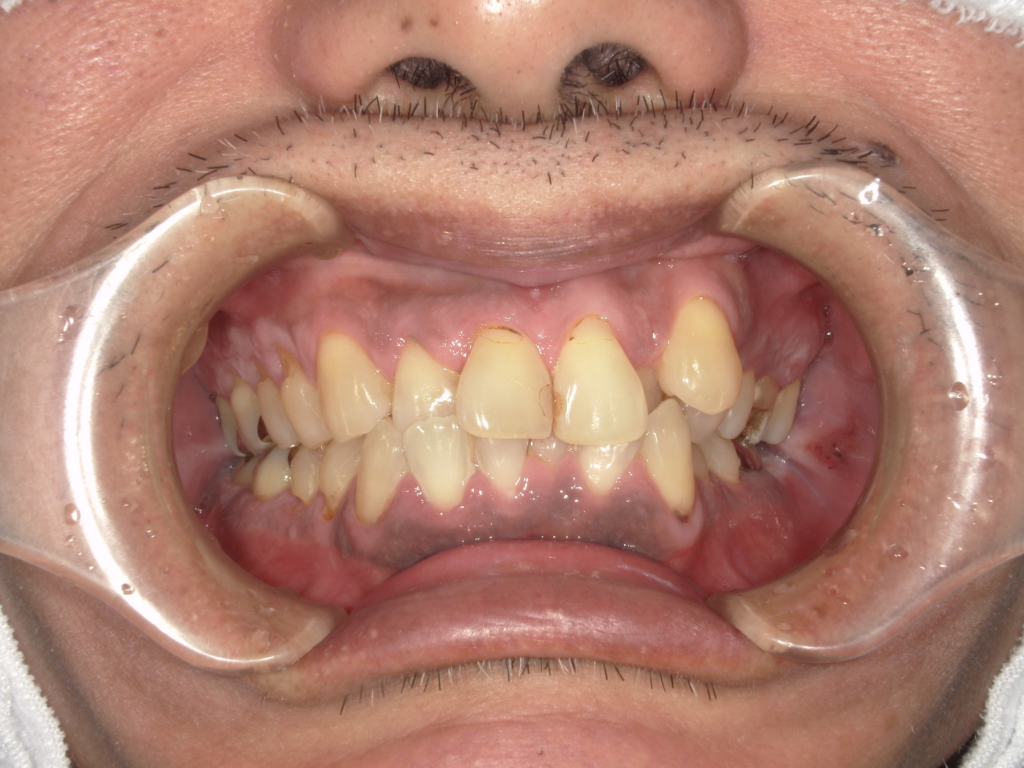

Y様インプラント実例 #44

左の上下の奥歯をインプラントで治療しています。

左下の奥歯は歯を抜くのと同時にインプラントの埋め込みを行っています。

被せものは上下、セラミックスで作っています。

治療前

治療後